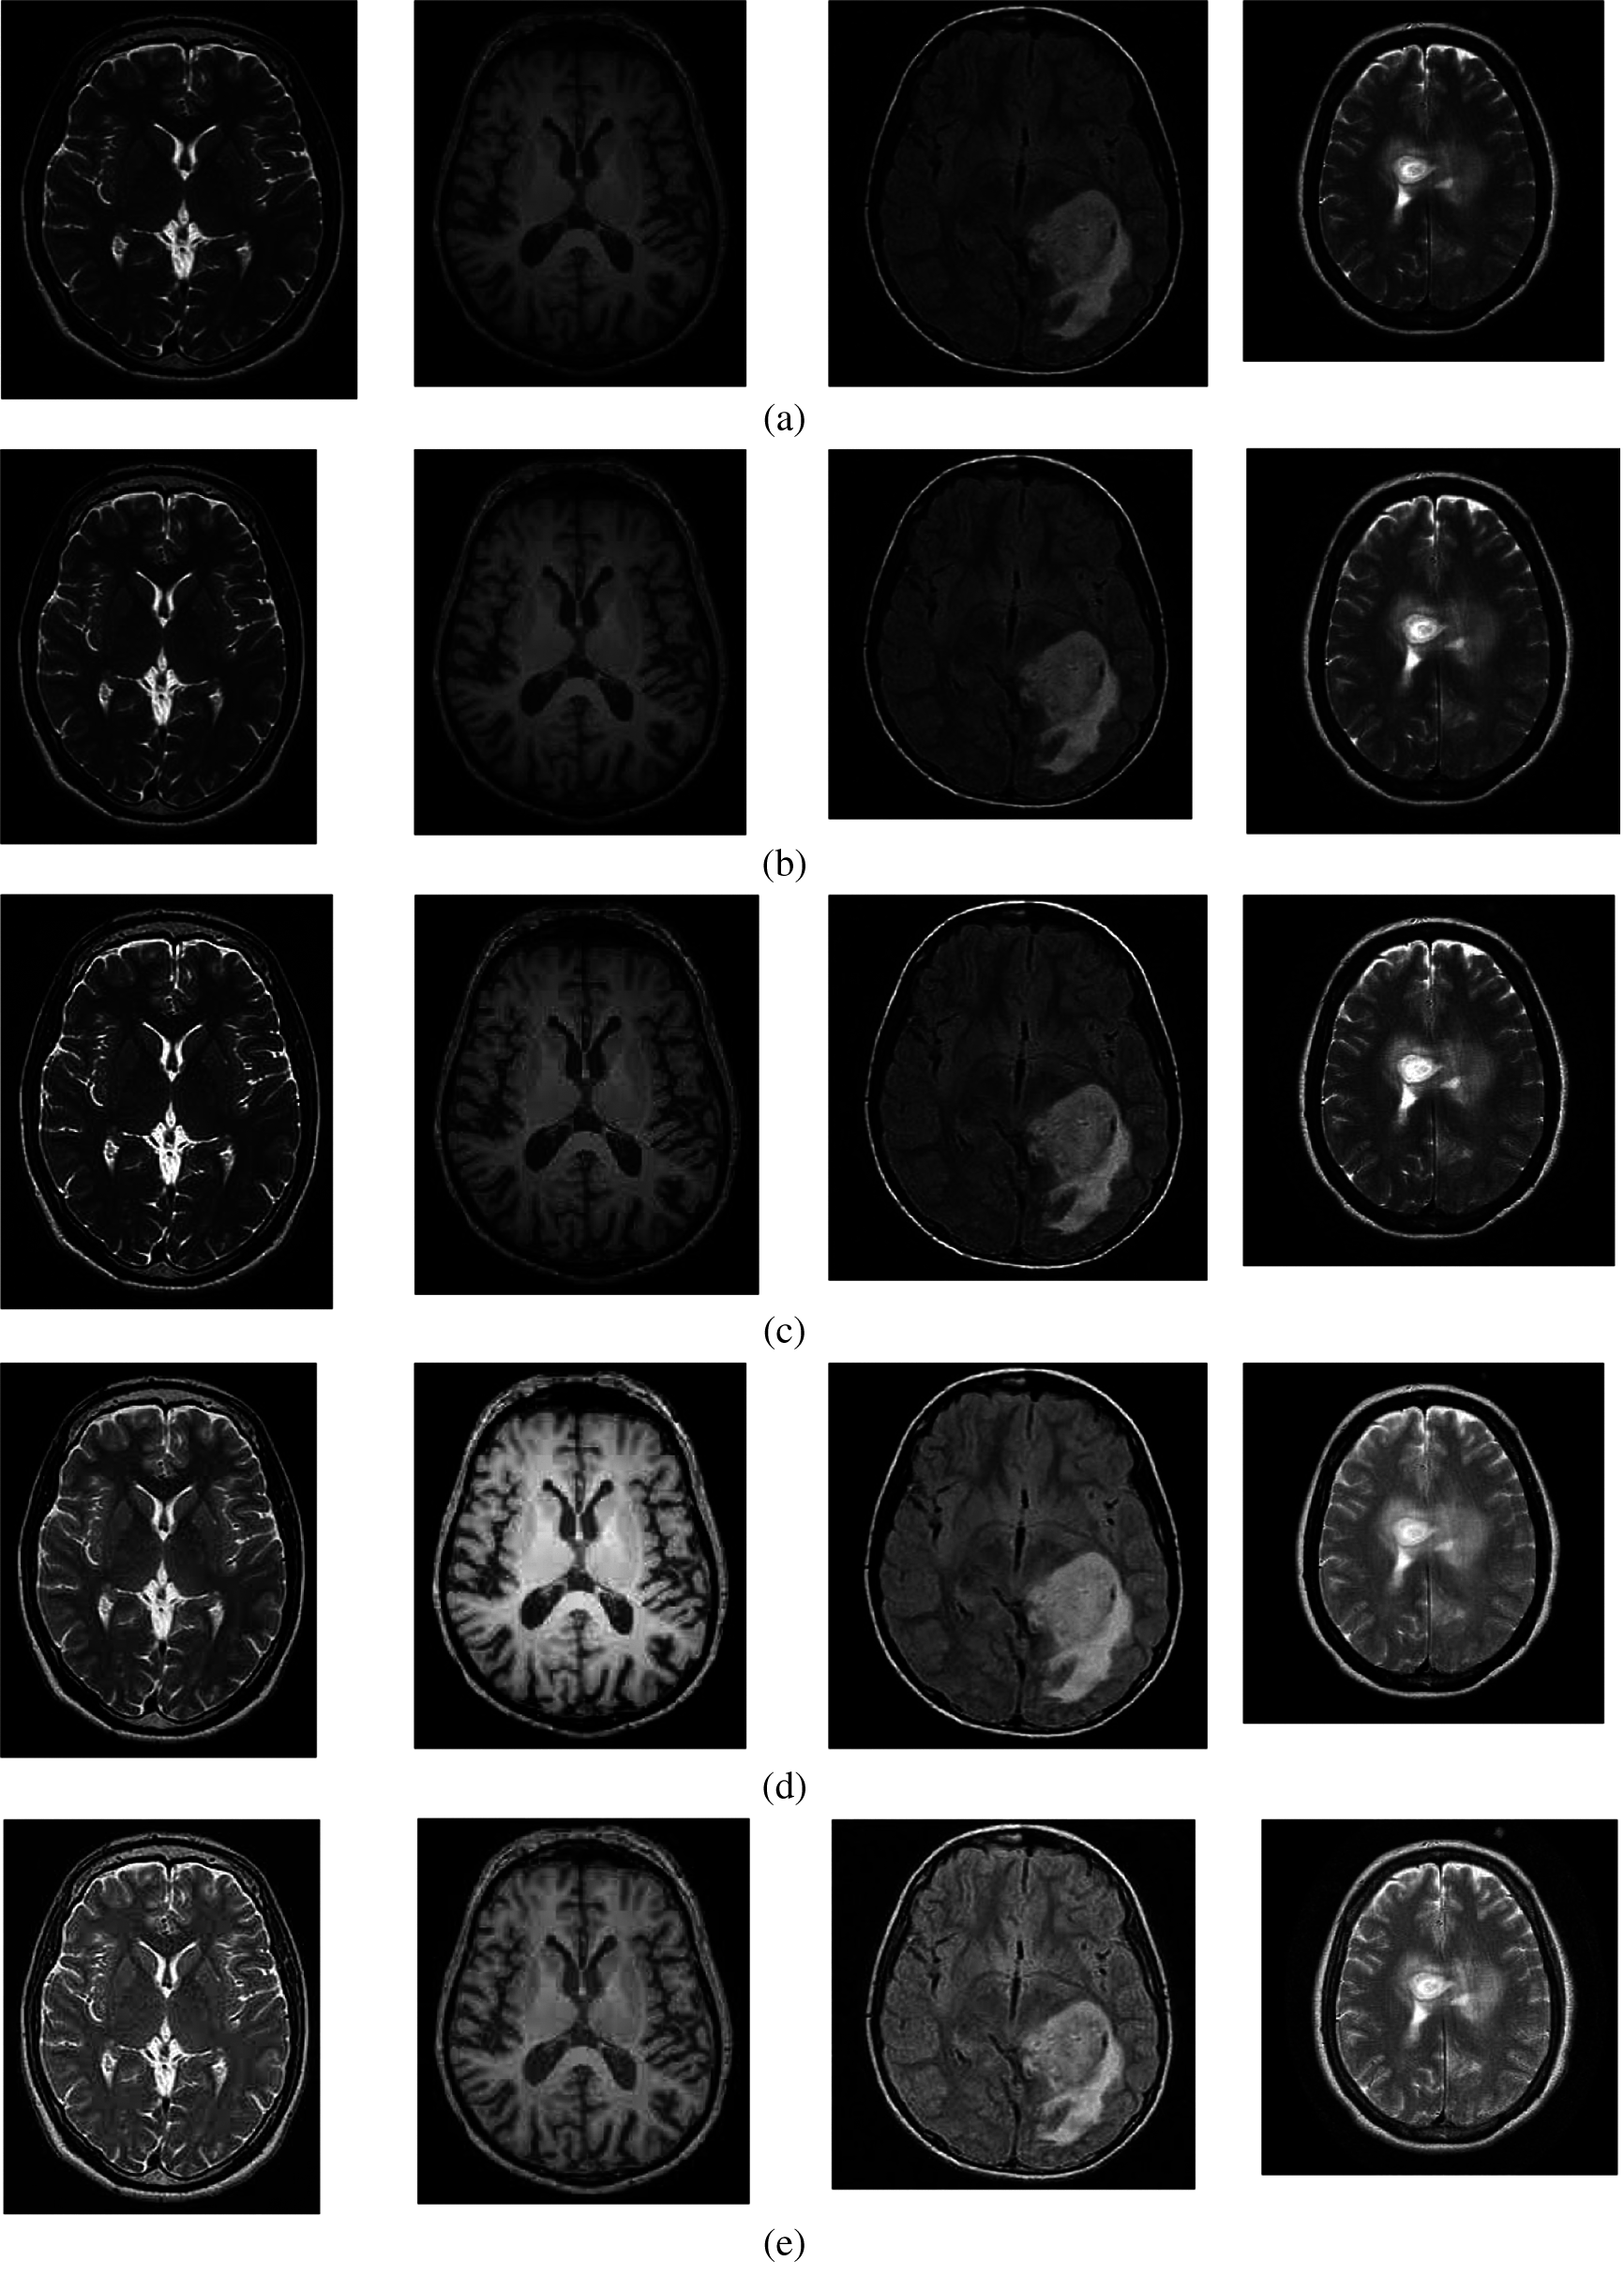

The qualitative results of the proposed and the existing methods are illustrated in Fig. 3. It can be seen that all of the images have different trends with the dark and bright areas. When we compare the enhancement results of existing methods with the suggested method, the proposed method shows better enhancement results than the existing methods in terms of image quality. In the case of the existing method, it could be seen that FPDEs methods [25] (Fig. 3f) produce over-enhanced images, while the proposed method yields natural appearance by enhancing the dark areas and maintaining the bright areas of input images.

Figure 3: The brain MRI enhancement results of the proposed and existing enhancement models. (a) Input image, (b) Al-Shamasneh et al., (c) Raghunandan et al., (d) Z. Al-Ameen, (e) X. Fu et al., (f) FPDEs, (g) Proposed method